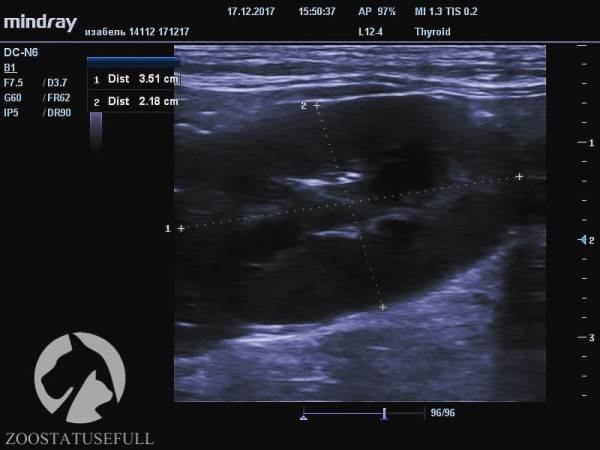

Здоровая почка кошки Изабель (обратите внимание на размер, указан в см)

Больная почка кошки Изабель

Но самое главное — воспалительный процесс, возникший в мочевыделительной системе на фоне «неотжимания» привёл к заболеванию, а потом и к «гибели» одной из почек. На снимках можно увидеть разницу между функционирующей почкой и нефункционирующей.

Это очень важно, обратите на это внимание — Изабель осталась с одной функционирующей почкой, потому что ее мочевой пузырь не опорожняли мануально, а не наоборот.